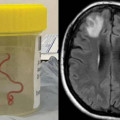

Այսօր գիտելիքի և դպրության օրն է. լուսանկար Աշխարհում առաջին անգամ կնոջ ուղեղում կենդանի որդ է հայտնաբերվել. ի՞նչ ախտանշաննե... Հայաստանում վաճառքի է հանվել HONOR 90 Lite-ը․ ոչ միայն գրավիչ, այլև բազմազան Ծեծի են ենթարկել ու առևանգել. Հրապարակվել է Ալեն Սարգսյանի լուսանկարը «Զվարթնոց» արգելոց-թանգարանում տեղի է ունեցել «Եվրոպական ժառանգության օրերի» փակ... Արջի քոթոթը Երևան-Վանաձոր ավտոճանապարհին վրաերթի է ենթարկվել (լուսանկար) Կուրսկում անօդաչու թռչող սարքը մխրճվել է բազմաբնակարան շենքի մեջ Սոնան իմ թևերն է դարձել. պատերազմում ձեռքերը կորցրած Վարազդատի հարսանիքն է Լիկա Մեսրոպյանը Խորեն Լևոնյանի մասնակցությամբ բացառիկ հրապարակում է արել՝ բաժանմ... Աննա Հակոբյանի ցուցադրած Էյնշտեյնի գիրքը հայտնվել է Ադրբեջանում գերեվարված հայ զ... Երգիչ Հայկոն այսօր կդառնար 50 տարեկան Նախկին ոստիկանապետի դստեր հանգիստը Փարիզում. լուսանկարներ Հացթուխը մի կտոր հաց տվեց Լուսեին․ հա՛մ ուտում է, հա՛մ ինձ տալիս (լուսանկարներ) Ադրիանա Գալստյանը նշանադրվե՞լ է. բացառիկ Ադրբեջանը հրապարակել է այսօր գերեվարված պահեստազորայինի լուսանկարը Ադրբեջանական սրբապղծություն՝ Դադիվանքում. լուսանկարներ Ողբերգական վթարից զոհված զբոսավարը 21-ամյա Մուշեղ Էլոյանն էր (ֆոտո) Հենրիխ Մխիթարյանի քույրն ամուսնացել է (լուսանկար) Էրիկ Էսրայիլյանը, Սերժ Թանկյանը և Քիմ Քարդաշյանը հրապարակումներ են կատարել Լաչին... Քիմ Քարդաշյանը ծանր վնասվածք է ստացել Կապանում հարկադիր քարաթափման աշխատանքներ են իրականացվելու «Ապրելու երկիր» կուսակցության համագումարն' ամփոփ (լուսանկարներ) «Ռուսաստանն ու Հայաստանը այսօր կարող են պայմանավորվել ամեն ինչում». Ռուսական գրք... Մաշ Իսրայելյանը լուսանկարներ է հրապարակել ամուսնու հետ Գ.Վ. Պլեխանովի անվան Ռուսաստանի տնտեսագիտական համալսարանի Երևանի մասնաճյուղն այս... Զոհված զինծառայող Լավրենտի սիրելին նրա հետ լուսանկար է հրապարակել Սիրուշոյի ոճային լուսանկարները Նյու Յորքից Բնական․ Մարջան Ավետիսյանն առանց շպարի 49-ամյա դերասանուհի Քեյթ Բեքինսեյլը Նյու Յորքի Նորաձևության շաբաթվա ընթացքում բե... Մոնիկա Բելուչիի շքեղ կերպարը` Վենետիկի 79-րդ կինոփառատոնին (լուսանկար)